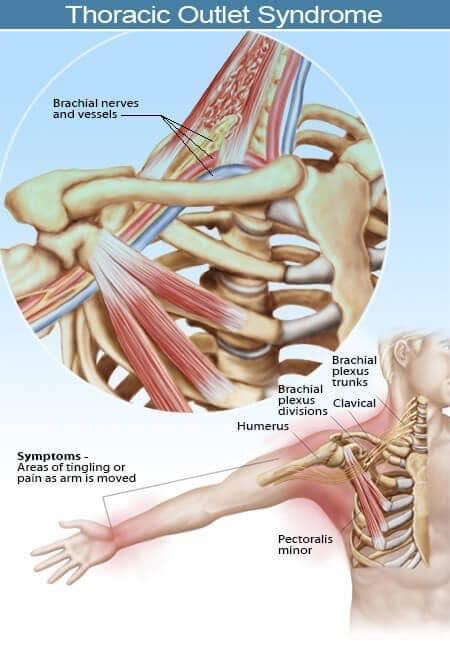

Hội chứng lối thoát ngực là một tình trạng, theo đó triệu chứng được tạo ra từ việc chèn ép các dây thần kinh, mạch máu, hoặc cả hai, vì một lối đi hẹp thông qua một khu vực (lối thoát ngực) giữa nền cổ và nách. Lối thoát ngực được bao quanh bởi cơ, xương và các mô khác. Bất kỳ tình trạng nào gây phì đại hay chuyển động của các mô hoặc gần lối thoát ngực đều có thể gây ra hội chứng lối thoát ngực. Các nguyên nhân thường gặp của hội chứng lối thoát ngực bao gồm chấn thương vật lý như một tai nạn xe hơi, tổn thương lặp đi lặp lại do công việc hoặc các hoạt động liên quan đến thể thao, một khuyết tật bẩm sinh nào đó (chẳng hạn như có một xương sườn phụ), mang thai, tăng cân, và các khối u ở phía trên của phổi (hiếm). Ngay cả một chấn thương dài trong quá khứ có thể dẫn đến hội chứng lối thoát ngực trong hiện tại. Đôi khi các bác sĩ không thể xác định nguyên nhân của hội chứng lối thoát ngực.

Hội chứng lối thoát ngực do căn nguyên thần kinh: loại này đặc trưng bởi sự chèn ép đám rồi thần kinh cánh tay. Đám rối thần kinh cánh tay là một mạng lưới các dây thần kinh xuất phát từ tuỷ sống, kiểm soát vận động của các cơ và cảm giác ở vai, cánh tay và bàn tay. Trong hầu hết trường hợp của hội chứng lối thoát ngực triệu chứng là về thần kinh.

Hội chứng lối thoát ngực do căn nguyên mạch máu: xảy ra khi một hoặc nhiều động mạch, tĩnh mạch dưới xương đòn bị chèn ép.

Hội chứng lối thoát ngực ảnh hưởng đến chủ yếu đến chi trên, đặc biệt là cánh tay và bàn tay. Cánh tay và bàn tay hầu như lúc nào cũng đau, đau liên tục. Bệnh nhân đau nhói, nóng. Cũng có thể, cơn đau chỉ có ở một phần của bàn tay, như mặt trong các ngón tay thứ 4 và thứ 5, hoặc cả bàn tay. Ngoài ra, bệnh nhân có thể đau ở mặt trong của cẳng tay và cánh tay, vùng cổ, vùng ngực dưới xương đòn, vùng nách, và lưng trên (như trong cơ thang và vùng cơ trám). Bên cạnh đó còn có cá triệu chứng khác như bàn tay xanh tím, tay này lạnh hơn tay kia, yếu cơ. Ngứa ran cũng có thể xuất hiện.

Triệu chứng hội chứng ngực lối thoát ngực có thể khác nhau, tùy thuộc vào những cấu trúc bị chèn ép. Khi dây thần kinh bị chèn, dấu hiệu và triệu chứng của hội chứng lối thoát ngực do căn nguyên thần kinh thường bao gồm:

Tê, ngứa ran ở các ngón tay

Đau vùng vai và cổ

Đau ở cánh tay hoặc bàn tay